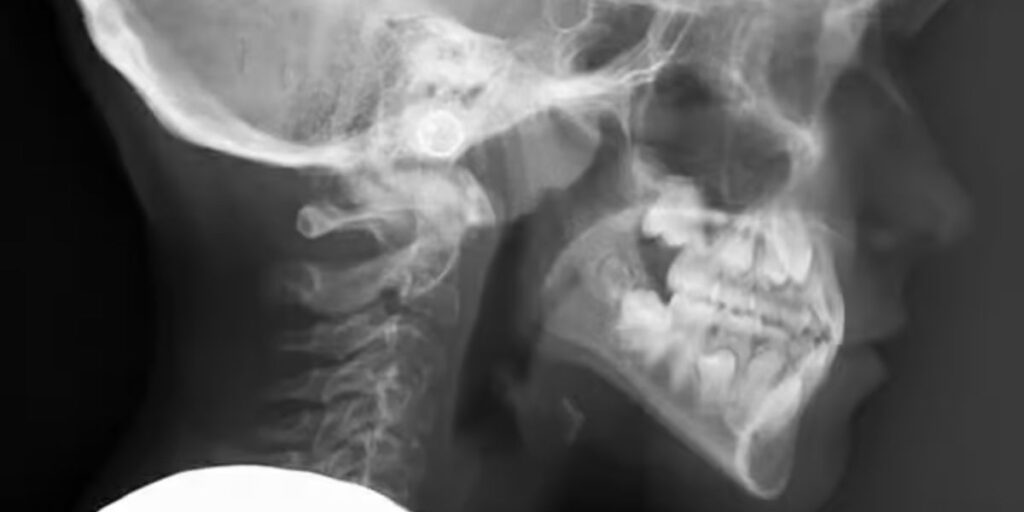

L’esame di Teleradiografia è una procedura diagnostica di fondamentale importanza nell’odontoiatria moderna. Grazie a immagini precise e dettagliate dell’apparato scheletrico facciale, questa tecnica consente ai professionisti di valutare con precisione la struttura ossea e l’allineamento dentale, facilitando diagnosi accurate e la pianificazione di trattamenti ortodontici mirati. Presso il Poliambulatorio S-Medical Group di Sora, l’esame di Teleradiografia viene eseguito con apparecchiature di ultima generazione, garantendo risultati affidabili e sicurezza per il paziente.

L’esame di Teleradiografia è una metodologia non invasiva che utilizza raggi X a bassa intensità per catturare immagini digitali ad alta risoluzione del cranio e della cavità orale. Questa procedura è indispensabile per studiare in profondità le caratteristiche ossee e dentali, individuando eventuali anomalie o alterazioni della crescita. La precisione delle immagini ottenute rende questo esame un punto di riferimento per l’analisi ortodontica e per il monitoraggio di diverse patologie facciali.